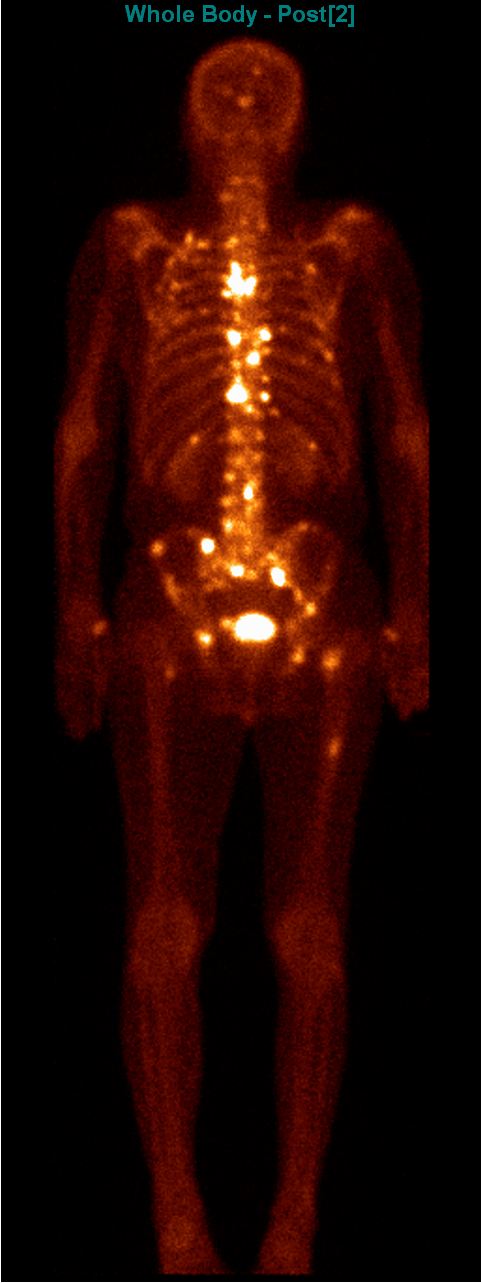

The most common clinical use of FDG-PET is in the form of whole-body scan, with oncologic indications. The majority of malignant tumors operate with higher energy consumption and show an increased glucose metabolism, consequently an increased uptake of FDG. The grade of malignancy is usually proportional to the rate of uptake. This method is useful in oncologic diagnostics, since it is capable to differentiate benign lesions from malignant ones. Whole-body PET imaging is capable to detect the primary tumor with local nodal metastases as well as distant metastatic lesions (staging) in one examination. (Figure 10.)

Test iframe

a

Image

b

c

d

10. Ewing’s sarcoma in the right humerus. Staging FDG PET-CT. PET Maximum Intensity Projection (MIP) image (a), transversal (b,c) and coronal (d) plane fused PET-CT images. Multiplex metastatic process with nodal, lung and bone involvement.